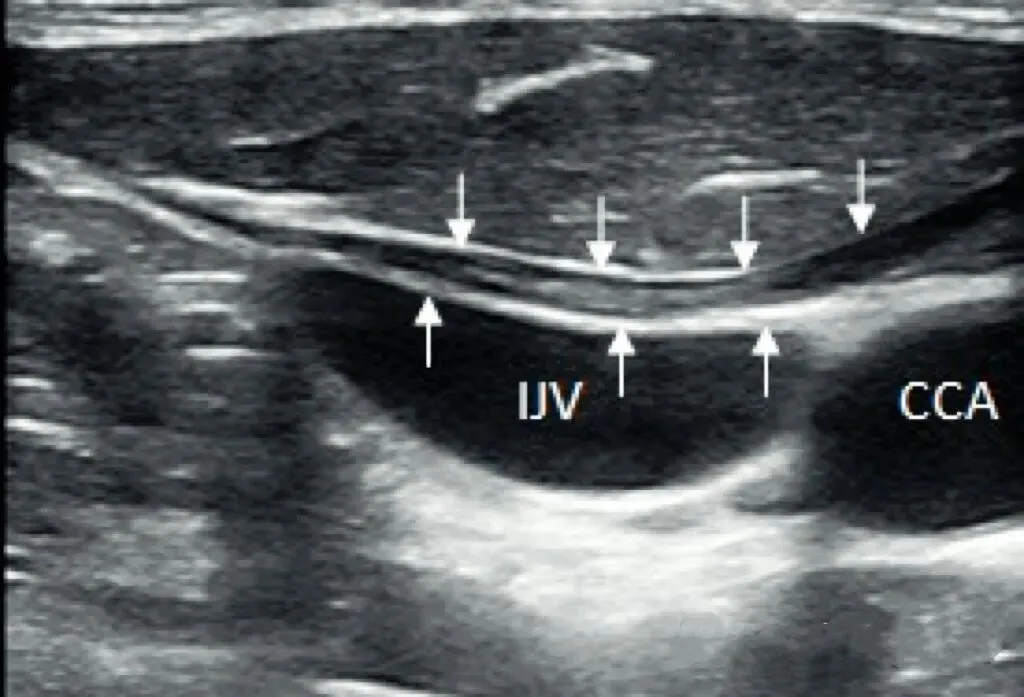

肩胛舌骨肌的超声成像

箭头示肩胛舌骨肌,IJV 颈内静脉,CCA 颈总动脉

肩胛舌骨肌主要作用为下降舌骨,在配合吞咽和发音中有重要作用。由于其起与肩胛骨,因此肩胛骨的位置变化对于舌骨的运动会有影响,需要注意排查。

临床疾病为肩胛舌骨肌综合征(OMS):患者于说话及吞咽时颈前部左或右侧(即三角肌外侧胸锁乳突肌中下部)向前突出一肿块,边界钝圆不清,吞咽动作完毕,则肿块随之消失,据此临床特点,则首先考虑本病。此外,此病主要需与甲状腺疾病、颈部肿大淋巴结相鉴别。